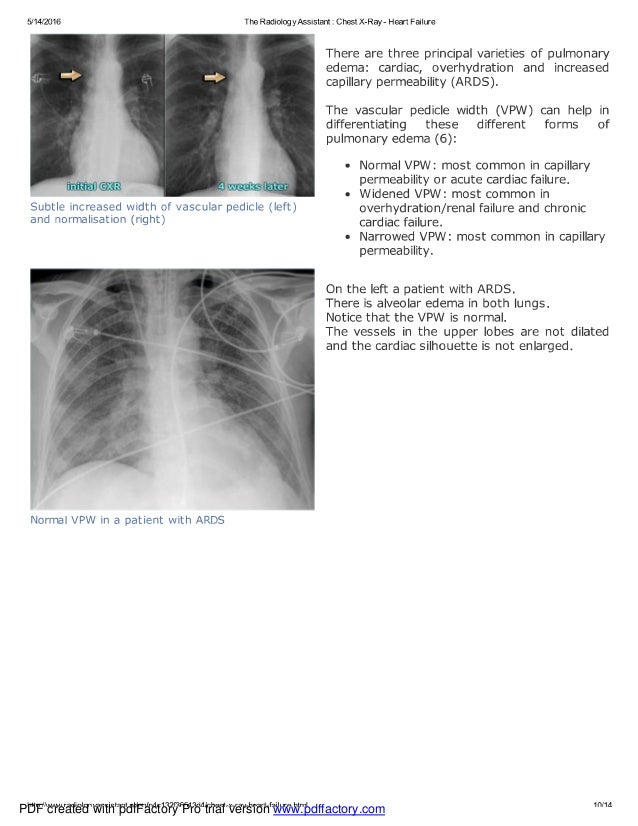

From radiologyassistant.nl

The Radiology Assistant Chest XRay Heart Failure Abcde Chest X Ray Heart Failure Kerley b lines (interstitial oedema) chest x ray examination. The chest x ray examination has an important role in the routine investigation of patients. Abcde Chest X Ray Heart Failure.

The Radiology Assistant Chest XRay Heart Failure Abcde Chest X Ray Heart Failure The chest x ray examination has an important role in the routine investigation of patients. Kerley b lines (interstitial oedema) chest x ray examination. Abcde Chest X Ray Heart Failure.

The Radiology Assistant Chest XRay Heart Failure Abcde Chest X Ray Heart Failure Kerley b lines (interstitial oedema) The chest x ray examination has an important role in the routine investigation of patients. chest x ray examination. Abcde Chest X Ray Heart Failure.

The Radiology Assistant Chest XRay Heart Failure Abcde Chest X Ray Heart Failure chest x ray examination. Kerley b lines (interstitial oedema) The chest x ray examination has an important role in the routine investigation of patients. Abcde Chest X Ray Heart Failure.